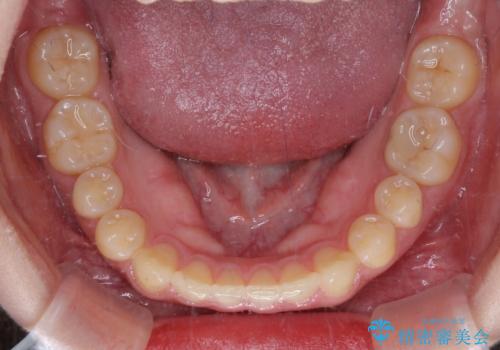

治療途中の奥歯と矯正治療の後戻り インビザライン・ライトによる矯正治療

- 根管治療を行ったままの奥歯と、矯正治療の後戻りを気にして来院された患者様です。

根管治療された歯に症状はなく、オールセラミッククラウンにて補綴治療を行うこととしました。

矯正治療の後戻りは軽微であったため、インビザラインの簡易パッケージであるインビザライン・ライトを用いて歯列を整えることとしました。

クラウンはよりよい咬み合わせで装着したいため、インビザラインを1セット使用して概ね歯列を整えた時点で補綴治療を行い、その後仕上げの矯正治療を行いました。